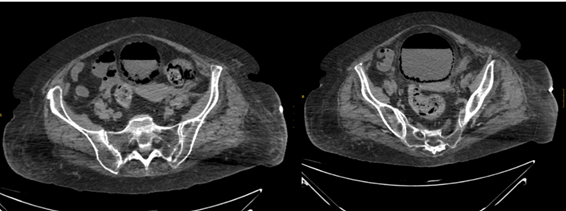

Ecografía abdominal: Hígado de tamaño, morfología y ecoestructura normales sin identificar LOEs. Colecistectomizada. Vías biliares de calibre normal. Páncreas no visualizable .Bazo homogéneo de tamaño normal. Aorta abdominal de calibre normal. No se identifican adenopatías retroperitoneales. Ambos riñones seniles con disminución del grosor parenquimatoso con leve hidronefrosis grado 1 bilateral. Vejiga distendida con marcada presencia de gas en toda su pared compatible con cistitis enfisematosa. Se decide realización de TC abdominal sin contraste urgente (Figura 2).

Se visualiza una hipoatenuación de densidad aire de localización parietal e intraluminal vesical correspondiente con hallazgos radiológicos compatibles con cistitis enfisematosa.

Figura 2 Imágenes de TC sin contraste, cortes axiales.